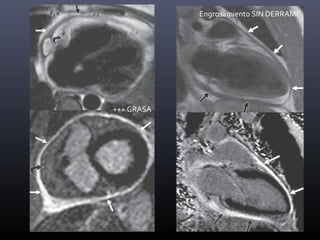

Engrosamiento SIN DERRAME

+++ GRASA

Engrosamiento DIFUSO

Engrosamiento FOCAL SIN Engrosamiento

ENGROSAMIENTO +

IRREGULAR

DERRAME

PLEURAL

VARIABLE

REALCE +

AFECTACIÓN

VENTRICULAR

-

PERICARDITIS

CRÓNICA

INFLAMATORIA